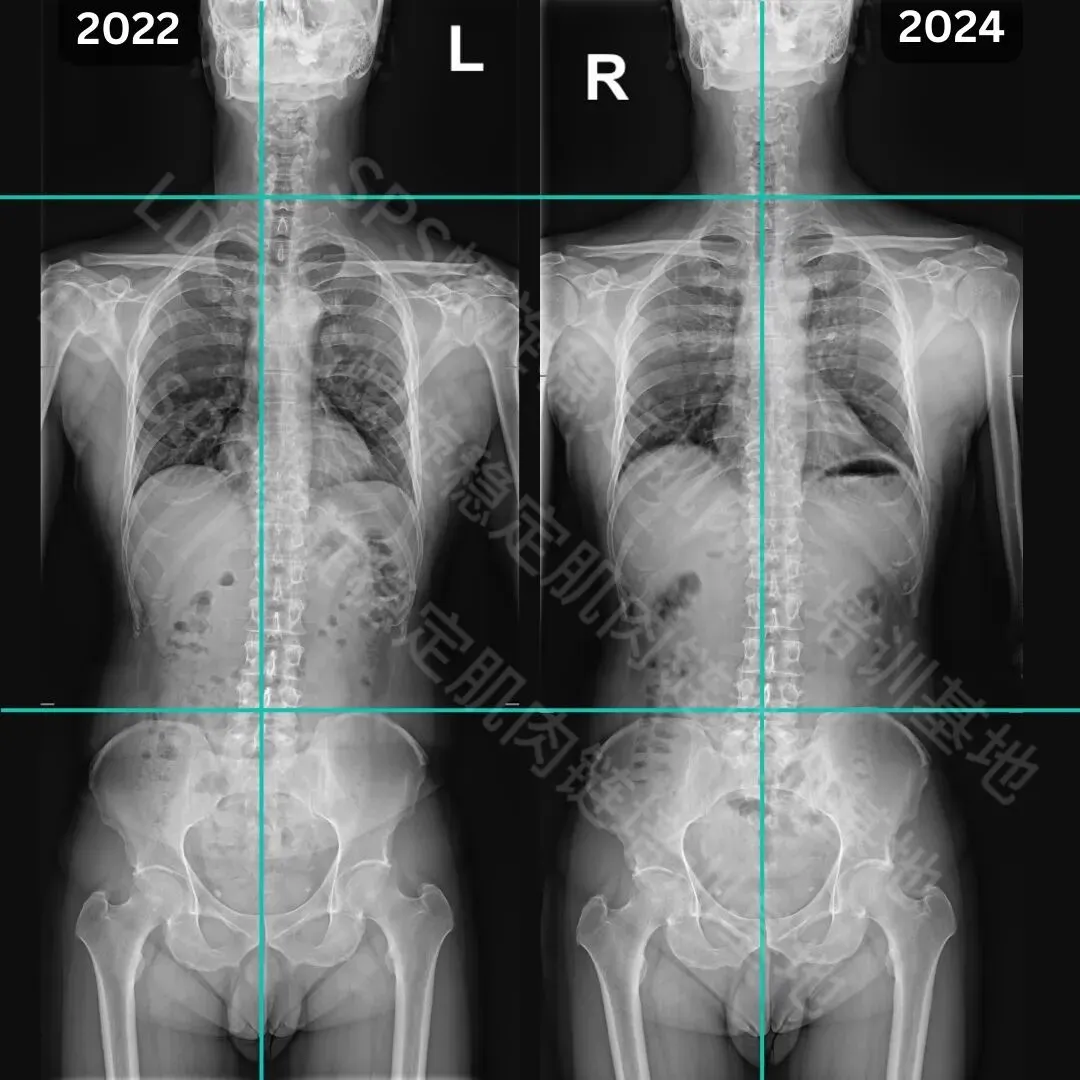

青少年侧弯改善案例

经过三个月的SPS螺旋稳定肌肉链训练

1.胸椎改善11度;2.骨盆旋转得到改善;3.体态、体轴得到改善。